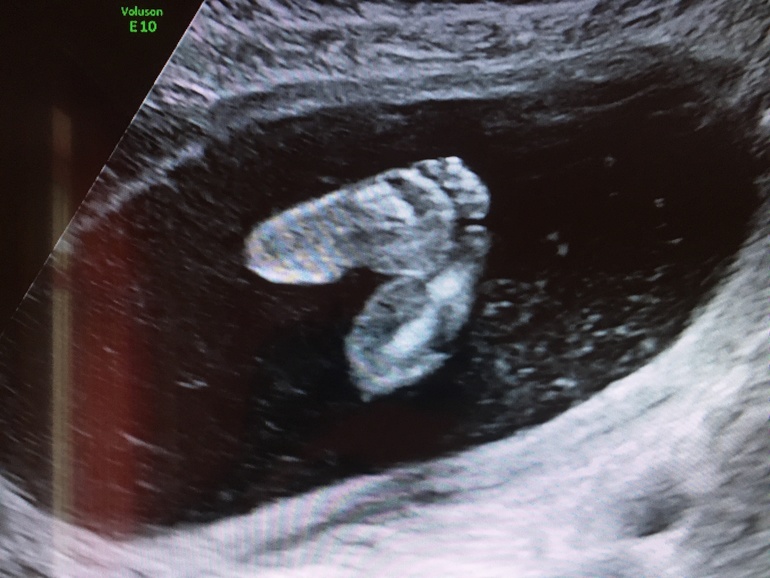

Ну и фото пяточек которые меня пинают )))

Это и вправду пяточки? Можно по ним пинетки вязать😄